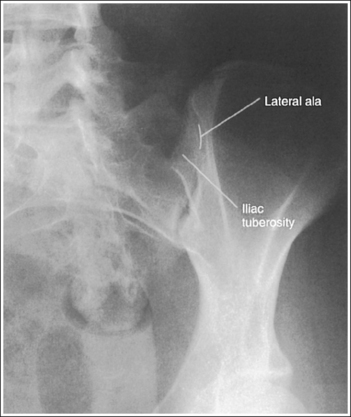

• Determining accuracy of obliquity. The accuracy of an AP oblique sacroiliac joint projection can be determined by the lack of ilium and sacral superimposition. The degree of separation or cavity demonstrated between the ilium and sacrum, which represents the sacroiliac joint, varies from patient to patient. The ilia and sacrum fit very snugly together and in older patients the joint spaces between them may be smaller or even nonexistent because of fibrous adhesions or synostosis. If the patient was not rotated enough to place the ilium and sacral ala in profile, the inferior and superior sacral aspects of the ala are demonstrated without ilium superimposition, whereas the lateral sacral ala is superimposed over the iliac tuberosity (see Image 25). The lateral sacrum is also demonstrated without ilium superimposition. If the patient was rotated more than needed to position the ilium and sacral ala in profile, the ilium is superimposed over the lateral sacral ala and the inferior sacrum (see Image 26).

IMAGE 25

The sacroiliac joint is closed. The superior and inferior sacral alae are demonstrated without iliac superimposition, and the lateral sacral ala is superimposed over the iliac tuberosity. The patient was not rotated enough.

Increase the pelvic obliquity. Because both the sacral ala and the ilium move simultaneously, the adjustment made should be only half the amount of superimposition of the sacral ala and iliac tuberosity.